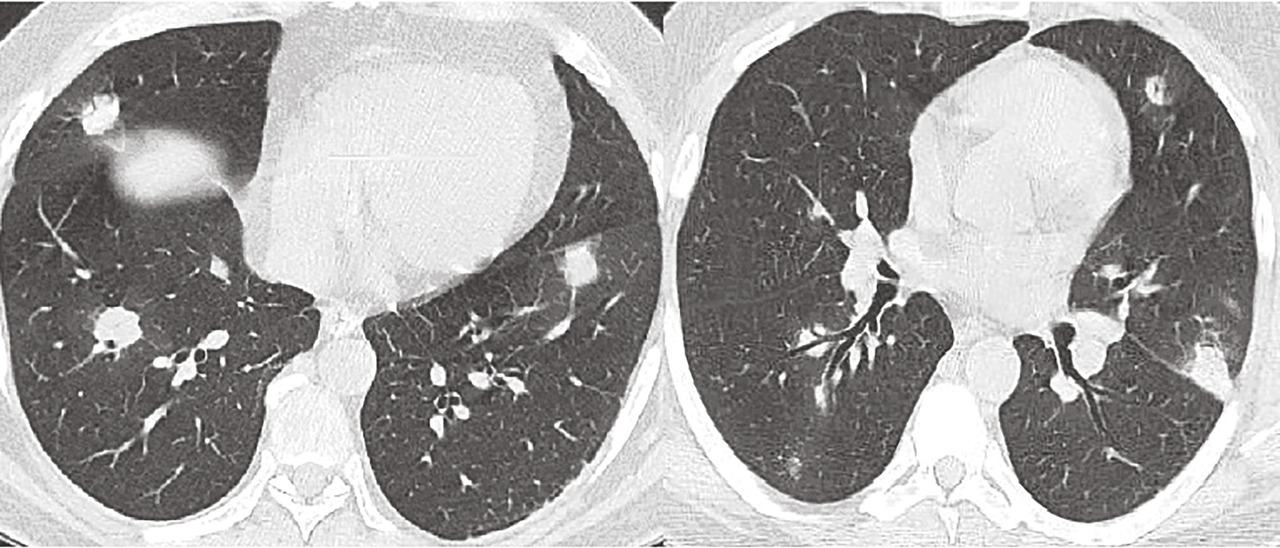

Cet homme de 46 ans était hospitalisé pour une hémoptysie fébrile. La tomodensitométrie thoracique montrait des nodules pulmonaires bilatéraux dont certains excavés (v. figure ). La protéine C-réactive était à 301 mg/L, la créatininémie à 80 μmol/L initialement mais la fonction rénale s’était dégradée en quelques jours avec un maximum 430 μmol/L. Une fibroscopie bronchique était réalisée ainsi que des biopsies ne mettant pas en évidence de tumeur. Une recherche d’anticorps anti-cytoplasme des neutrophiles (ANCA) était alors demandée en urgence : ils étaient fortement positifs avec fluorescence de type cytoplasmique et spécificité de type PR3. Le diagnostic final était celui d’une granulomatose avec polyangéite (anciennement maladie de Wegener). L’évolution était favorable après un traitement immunosuppresseur lourd (bolus de Solumedrol et de cyclophosphamide puis entretien par rituximab) associé à des échanges plasmatiques à la phase initiale.

Devant des images pulmonaires nodulaires, a fortiori excavées, il est important de savoir évoquer des causes non tumorales, notamment des infections (tuberculose, abcès, endocardites) et des maladies de système (histiocytose X, polyarthrite rhumatoïde, vascularite à ANCA).1 Cet enjeu diagnostique est fondamental dans les vascularites à ANCA car le pronostic est en partie lié à la rapidité du diagnostic et à la mise en place d’un traitement spécifique, notamment lorsqu’il existe un syndrome pneumo-rénal.2